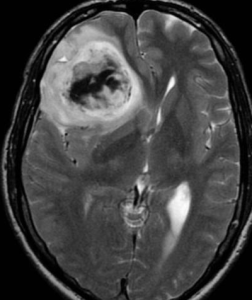

腦部膠質瘤為膠質瘤中最常見的一種,約占40%左右。病理分型為Ⅰ級(星形細胞瘤),Ⅱ級(星形母細胞瘤),Ⅲ~Ⅳ級(多形膠母細胞瘤)。Ⅰ~Ⅱ級星形細胞瘤為低度惡性,起病緩慢,腫瘤在CT及MR的表現多為實性或囊性,邊界不清,腫瘤實性部分或囊性結節均可強化。臨床表現與病灶部位不同進行性地出現相應的症狀,並最後出現顱高壓的症狀。Ⅲ~Ⅳ級的多形膠母細胞瘤起病快速,為惡性度最高的腫瘤,多生長於大腦半球,因腫瘤生長迅速,腫瘤中心可有多處壞死及出血,CT及MR均明顯強化。周圍可伴大片腦組織的水腫。